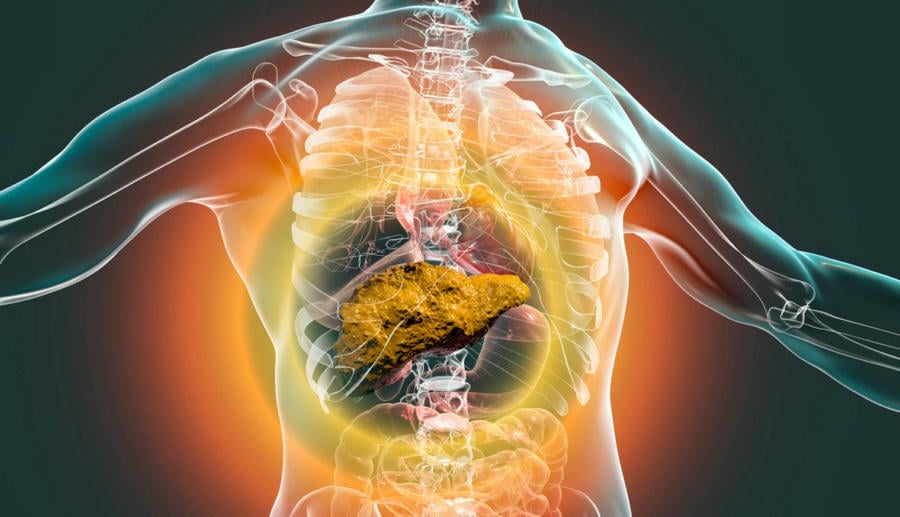

கல்லீரல் சிரோசிஸ் என்றால் என்ன?

ஆரோக்கியமான கல்லீரல் செல்களை அழற் (scar) திசைகள் மாற்றும்போது, கல்லீரல் சிரோசிஸ் போன்ற நோய்கள் ஏற்படுகின்றன. கல்லீரலின் ஜீரணம், புரத உற்பத்தி (இரத்த உறைப்புக் காரணிகள் உட்பட) மற்றும் மருந்து மற்றும் நச்சு வடிகட்டல் போன்ற முக்கிய செயல்பாடுகள் பாதிக்கப்படுகின்றன. ஆயுர்வேதத்தில் கல்லீரல் சிரோசிஸ் குணமடைதல், சில இயற்கை மூலாதாரங்கள் மற்றும் குணமடைதலின் தரத்தை மேம்படுத்தும் செயல்முறைகளின் மூலம் பெறப்படுகிறது.

கல்லீரல் சிரோசிஸ் ஆயுர்வேத சிகிச்சை கல்லீரல் நிலையை உயிர்ப்பூண்டுவதையும், அதன் செயல்பாட்டையும் மேம்படுத்துவதையும் நோக்குகிறது. சிரோசிஸ் என்ற நோய், அதிகமான அழற் திசைகள் உருவாகுவதால் காலப்போக்கில் மோசமாகி விடுகிறது. ஆரம்பத்தில், உங்கள் உடல் குறைந்த கல்லீரல் செயல்பாட்டை சமநிலைப்படுத்த முயற்சிக்கும் போது, அதனை நீங்கள் அதிகமாக கவனிக்கக்கூடாது.

கல்லீரல் சிரோசிஸின் சிக்கல்கள் என்ன இருக்கலாம்?

கல்லீரல் சிரோசிஸ், சரியான நேரத்தில் சிகிச்சை செய்யப்படாவிட்டால், கடுமையாக மாறக்கூடும். இதன் சிக்கல்கள் பின்வருமாறு:

- குறைந்த நோய் எதிர்ப்பு சக்தி

- ஹார்மோன் சமநிலையின்மை

- ஜீரண மண்டல இரத்தசோகை

- திரவம் வெளியேற்றம், அதனால் ஏற்படும் அழற்சி

- நீண்டகால கல்லீரல் தோல்வி